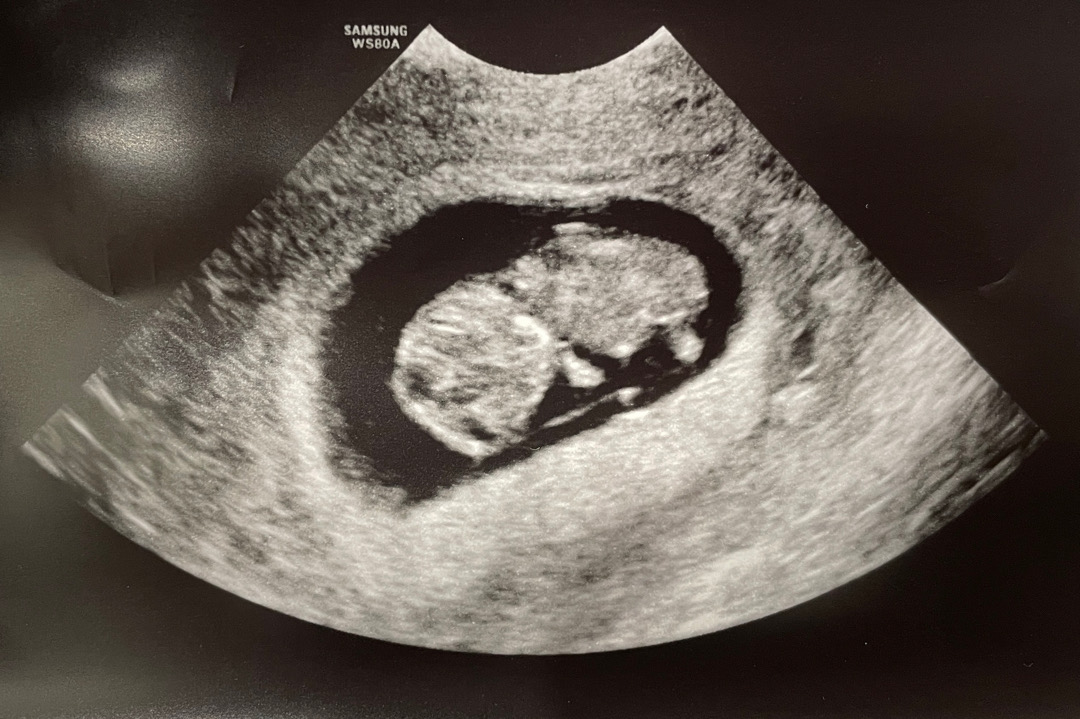

9주2일차 젤리곰

귀여운 젤리곰 보고 왔어요!ㅎㅎ 팔다리 슉슉 나와있는데, 넘 작고 소중하네요ㅎㅎ 다음 진료는 거의 4주 후로 잡혔는데, 기다릴 수 있을까요..ㅜㅜㅋㅋ